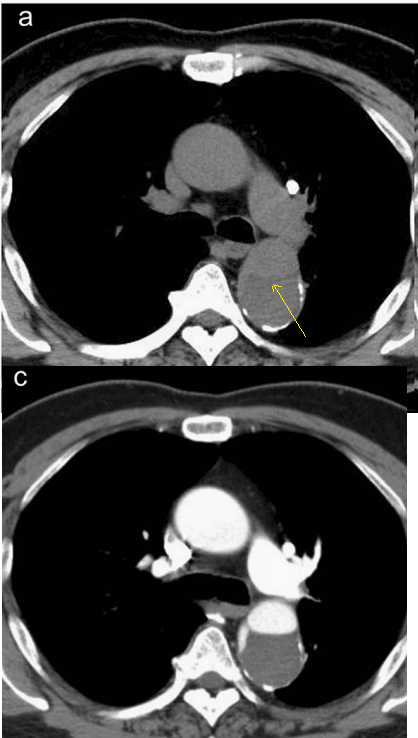

查到一篇文献,作者虽然用箭头标记了,并且是增强CT,但是鲁迅说:我大约肯定没有看出来,这是主动脉夹层!

图21